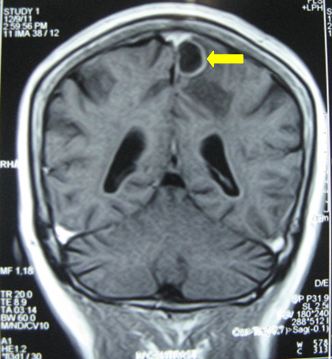

Chụp MRI sọ não (12/12/2011):

Hình 2: Hình ảnh chụp MRI sọ não có khối u não vùng đỉnh trái, 20×19mm, ngấm thuốc quanh u